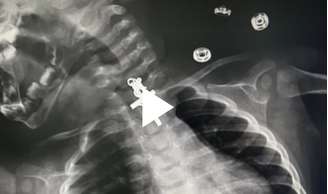

Raio-X mostra crucifixo preso em garganta de bebê

Raio-X mostra crucifico preso em garganta de bebê

Um bebê de 10 meses deu um grande susto na família no Peru ao ficar com um cruficixo preso na garganta. A descoberta aconteceu após a criança passar por um raio-x para encontrar o motivo do desconforto.